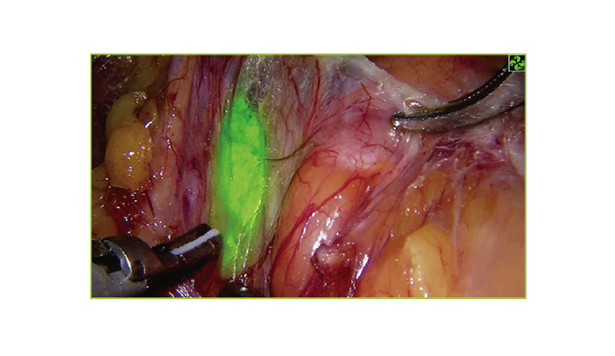

熒光攝像系統實時捕获吲哚誓綠被

激發的熒光信號成像,,,,,,,,與相同視野

的白光圖像同步精準疊加,,,,,,,,達到

術野熒光定位及導航的目的。。。。。。。。